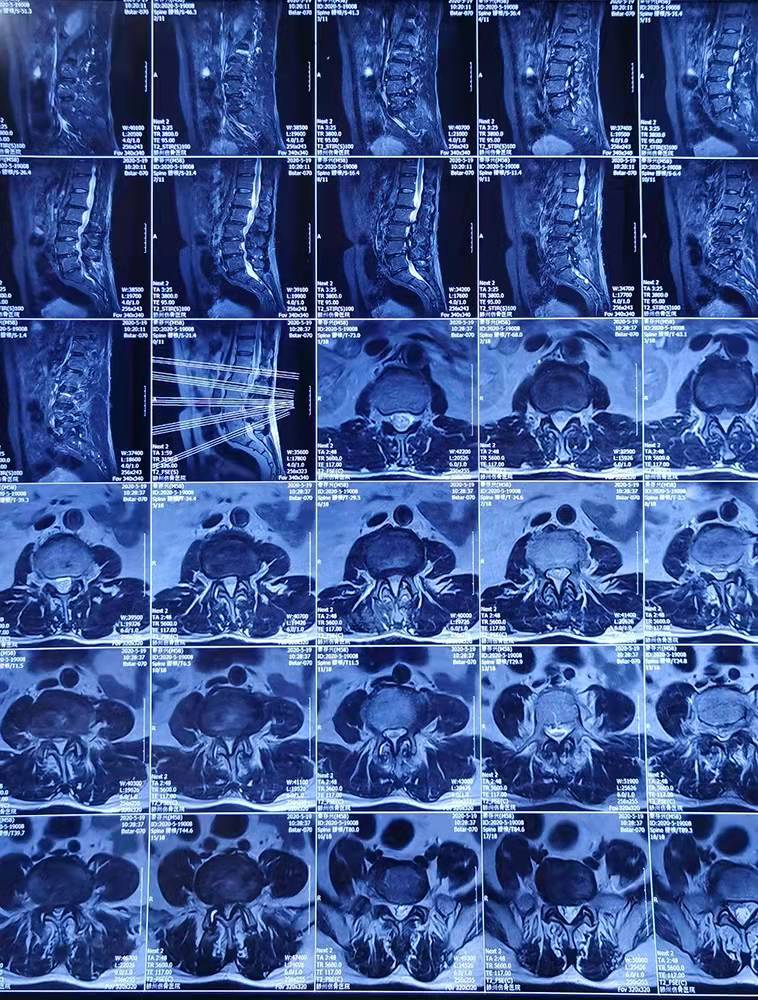

患者秦存興,男,59歲,腰痛多年勞累后加重,近一年來感腰痛伴雙側(cè)臀部、左大腿外側(cè)、小腿外側(cè)及右足麻木,行走50米后即感雙下肢疼痛劇烈,病痛的折磨給患者的生活帶來了很大的痛苦,讓他對未來失去了信心。來到誠德骨科醫(yī)院

經(jīng)查體、X片、CT及核磁共振檢查后確診為腰椎管狹窄癥,腰椎退變性滑脫,與患者充分溝通后決定行腰1-腰5減壓植骨內(nèi)固定術(shù)